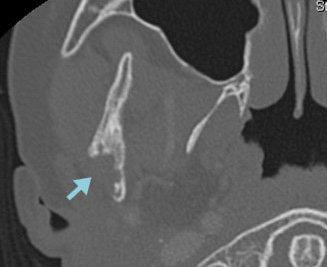

右下顎骨にLCHの骨再発をきたした。HU内服治療を開始後、溶骨部分の順調な修復が認められた。

CT 骨条件

ハイドロキシウレア開始時